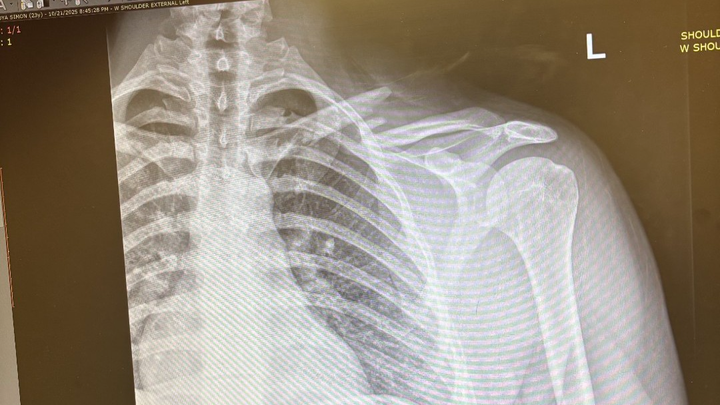

Hello, my name is val and I'm creating a gofund me for my younger brother Simon, who had an accident, unfortunately while training he broke his collarbone in two places and required surgery with plate and screws, along with a physical therapy. He won't be able to work for 10 weeks and the medical bills will be coming soon, that he won't be able to pay, our family is trying our best to help but it isn't enough, if you can help to contribute I would greatly appreciated it.